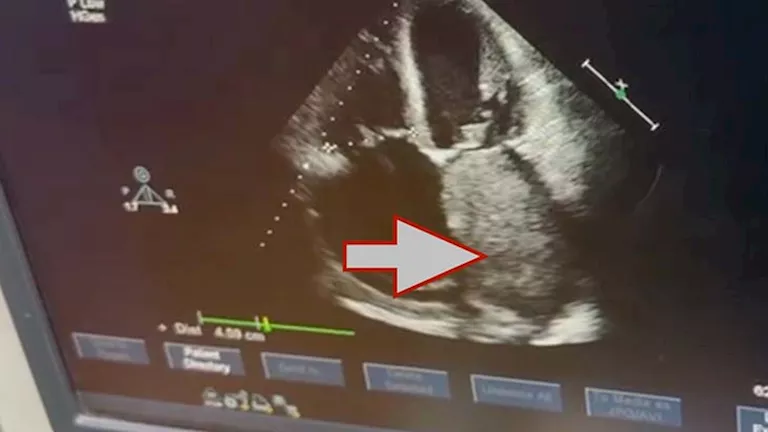

استئصال ورم نادر من قلب مريض سبعيني بقصر العيني نجح فريق جراحة القلب والصدر بكلية الطب جامعة القاهرة في إجراء جراحة قلب معقدة لاستئصال ورم ضخم من داخل الأذين الأيسر…